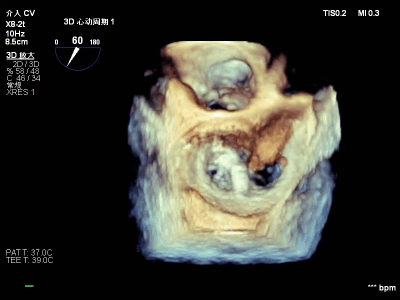

【术中操作(含关键步骤超声)】

鉴于患者术前心功能差、多支架植入的特殊情况,手术全程需兼顾“精准操作”与“保护心功能”双重要求:在全麻与经食道超声的协同引导下,团队先突破心功能受损导致的术野稳定性难题,稳步经心尖建立手术轨道与输送鞘;随后聚焦二尖瓣2偏3区精准置入一枚Ⅱf型夹合器,成功攻占这一解剖位置深、毗邻结构敏感、容错率极低而操作难度陡增的区域。

手术中,主刀术者常青教授稳定发挥,经过严谨的策略思索,挑战超精细微调整与瞬间捕获夹合,逐步逆转反流症状。从显著改善到最终完全消除,全程仅约25min的导管操作时长。在高危病例的严苛挑战下,凸显了团队操作的娴熟度与安全性。